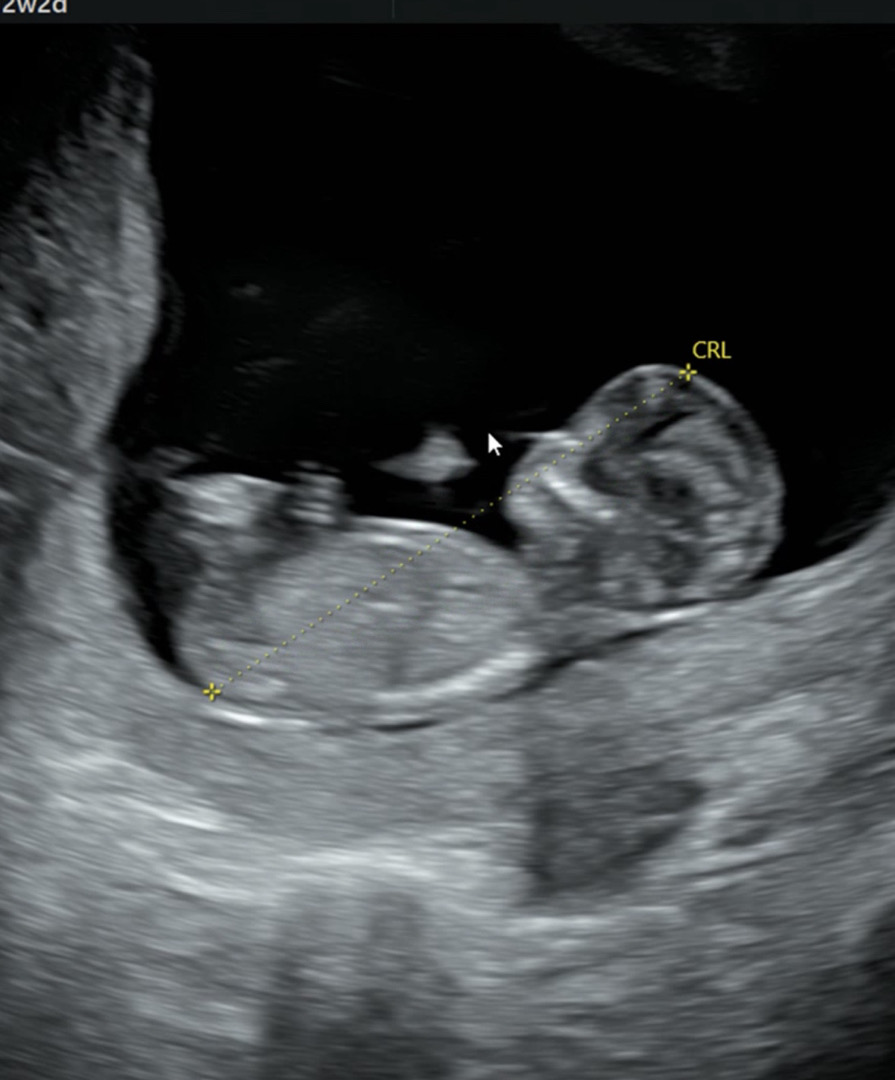

12주 2일때 정밀초음파때 찍은 사진인데 이 사진만 보고 예측가능할까여?ㅠㅠㅠ여러분 성별 의견 부탁드릴게요🥹🥹(각도법 사진 이렇게 올리는거 맞겠죠..?😅)

이 사진은 생식기가 안 보이는 것 같아요!